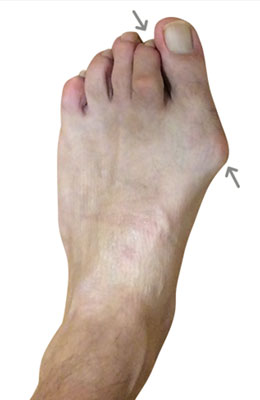

Before

Minimally Invasive Bunion Surgery before

After

Minimally Invasive Bunion Surgery after

Minimally Invasive Bunion Surgery featuring the miniBunon™ System and Tailors Bunionectomy

Melissa is a 32-year-old businesswoman who could not be off her foot post-surgery, yet she had a severely painful bunion. We performed our miniBunon™ System (our trademarked minimally invasive bunion surgery) and had a dramatic correction with no downtime. Melissa continued to work after her bunion surgery and was back in shoes and full activity at 5 weeks. Melissa could not believe the results of her Bunionectomy resulting in no bony bump, no scar and amazing motion. “After” picture taken immediately following surgery. Note the bunion and bunionette (Tailor’s bunion) in the before picture.